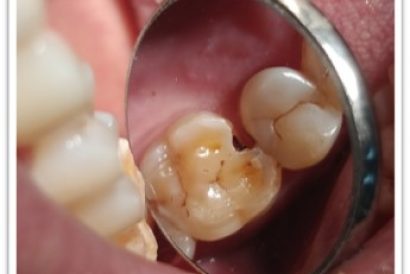

Patient Name:Akshay Gharat

Tooth Involved :16

Diagnosis :Caries Involving Enamel And Dentin Mesiocclusally

Treatment :Class Two Direct Composite Restoration Using Nanohybrid Composite

Before

After